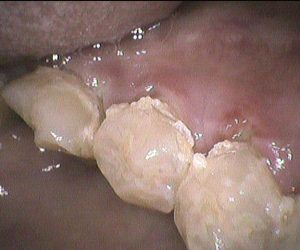

今日のクリーニングです🦷 歯科医院は30年以上ぶりだという患者さんです。 下の前歯の表側と裏側のクリーニング前後のお写真です📸 歯と歯の間や、歯ぐきのきわには歯石が多く付 […]